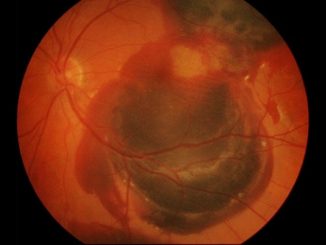

Study: AMD Gene Therapy Demonstrates Vision Stabilization

Dr Christine Kay A gene therapy that aims to increase levels of two key proteins that enable the growth of […]